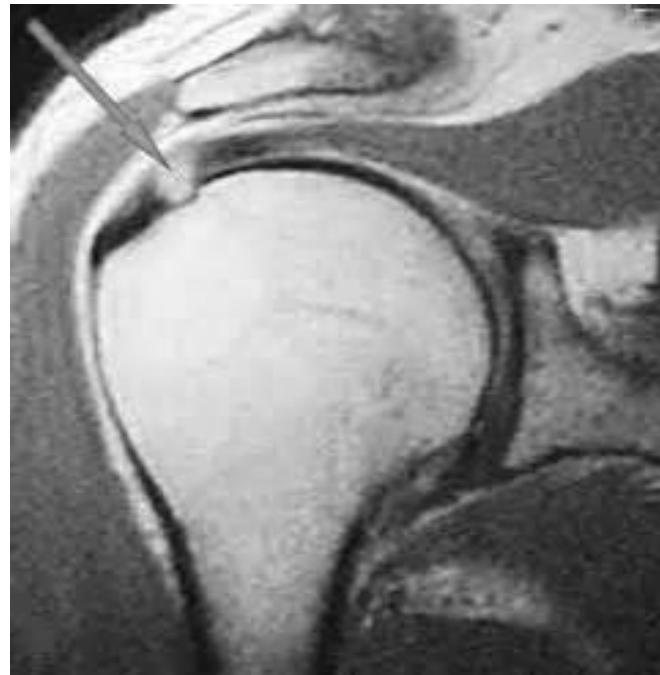

| Special Tests | Rotator Cuff Power (compare both sides): • Instability (Bankart): Apprehension Test (abduct and externally rotate arm, apply anterior pressure, watch patient’s face). • Supraspinatus (Empty Can Test): Flex shoulder to 30° with thumbs down; ask patient to resist. • Impingement tests: Neer’s Impingement Test, Hawkins’ Impingement Test. or neer’s rotator cuff + abduction resistance for supraspinatus • Infraspinatus: Ask patient to perform external rotation against resistance (elbows at 90°). • Subscapularis: Ask patient to perform internal rotation against resistance OR use the Lift-Off Test. • Teres Minor: Ask patient to perform external rotation against resistance in 90° of shoulder abduction. • Biceps Tendon: Speed’s Test (resisted shoulder flexion with elbow extended and supinated) OR Yergason Test. • Deltoid: Axillary nerve assessment: Motor (active abduction - then drop test- Deltoid), Sensory (upper lateral aspect of arm). Serratus Anterior - Scapular Winging; long thoracic nerve: push against wall - observe back • AC Joint: Cross Body Adduction Test. • Muscle power tests: Abductors/Adductors, Internal/External Rotators, Serratus Anterior (winging), Biceps Brachii. | Apprehension test: Neer’s Impingement Test: Yergason Test: External / Internal Rotators Strength Test: Supraspinatus Test: Serratus Anterior - Scapular Winging; long thoracic nerve: Biceps Tendon & Ruptured long head: ![]() |

Q17: What is the following test name and what does it test?

Apprehension test for anterior shoulder instability